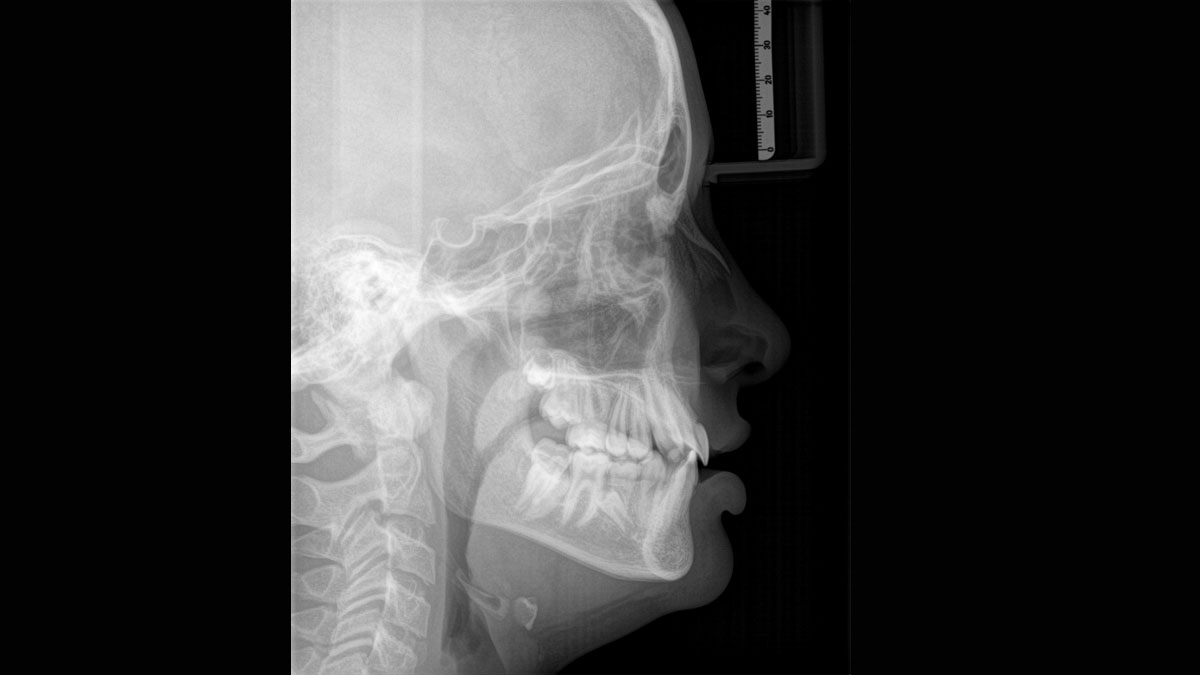

The patented bite block technology, for example, automatically establishes the correct inclination of the patient's head, positioning the patient in the occlusal plane, partnering with the 3 point head fixation and firm handles to ensure stable positioning-limiting unnecessary correction scans.